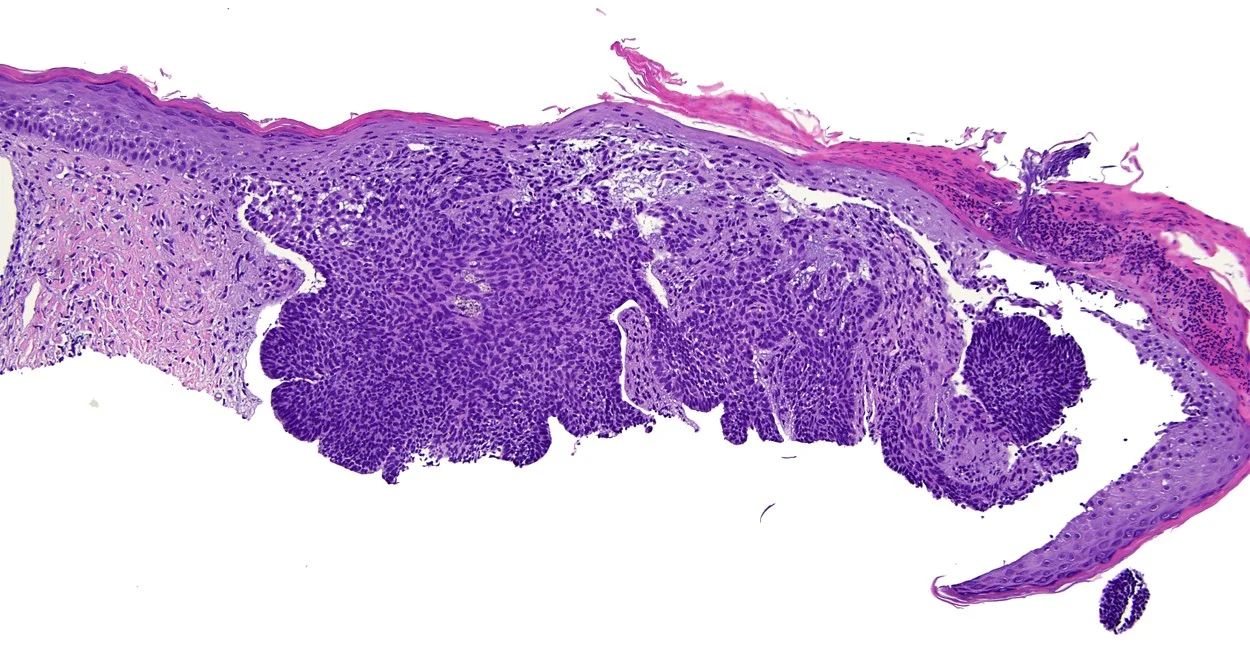

Can you name the type of skin cancer?

See if you can identify this common skin cancer based on what you have learned about the layers of the skin. Hint: The cells composing this growth resemble what layer of the epidermis?

Basal Cell Carcinoma

- Most common form of skin cancer.

- Composed of cells that resemble basal keratinocytes.

Basal Keratinocytes